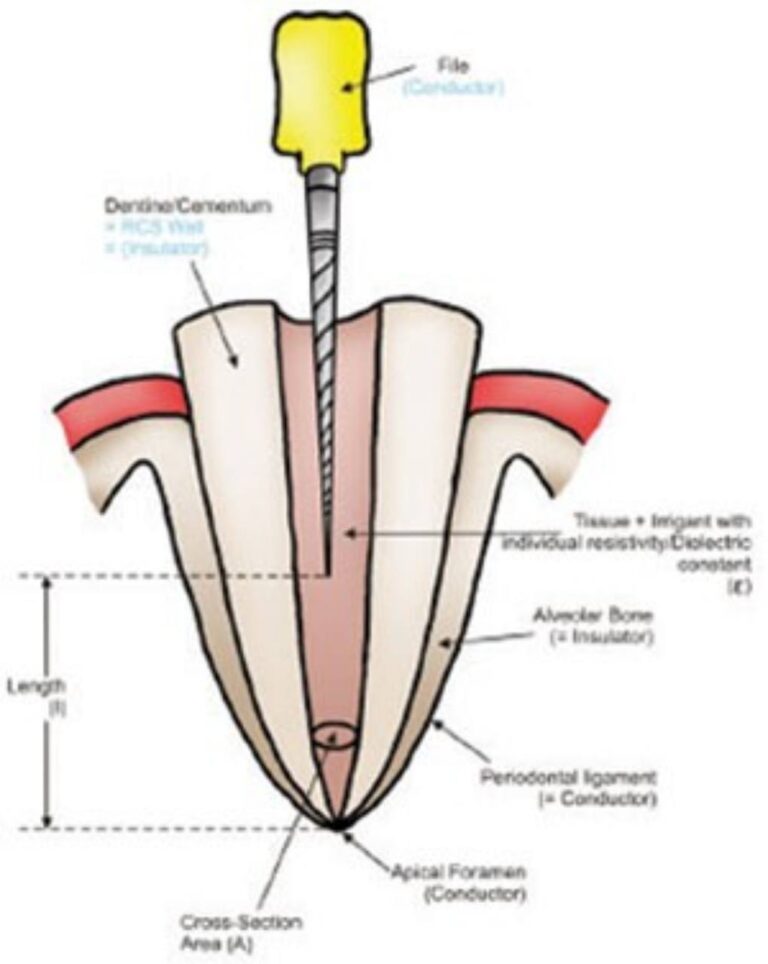

درمان ریشه یکی از حساسترین و دقیقترین درمانهای دندانپزشکی است و کوچکترین خطا در طول کار میتوان…

درمان ریشه مجدد یا اندودانتیک مجدد (Re-Endo)، یکی از درمانهای تخصصی دندانپزشکی است که زمانی انجام …